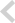

BEFORE & AFTER

- 덧니교정